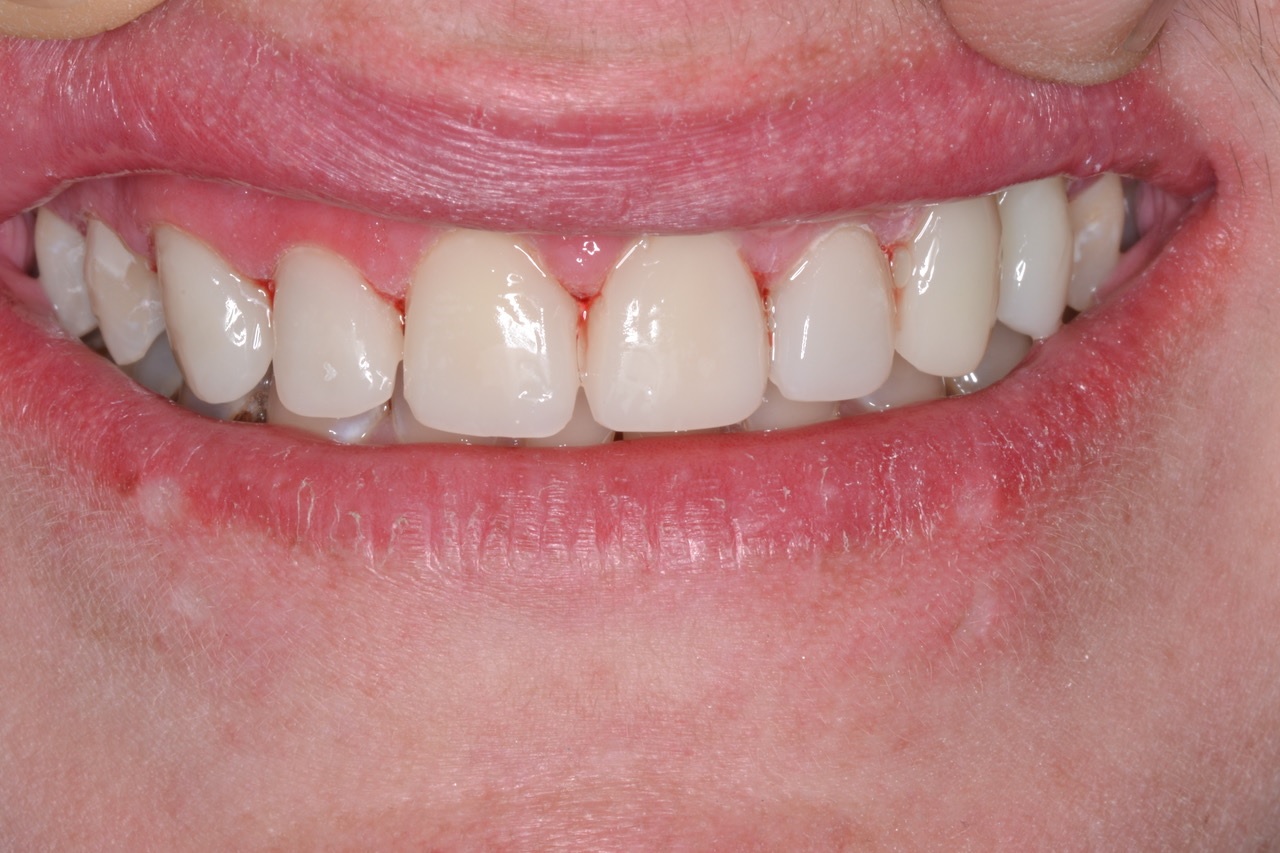

Sally suffered from years of neglect, trauma, and abuse. Her teeth were a disaster, but her life was turning around, and she wanted to save her smile and regain her self-confidence. (Fig. 1)

Figure 1

Figure 1. Pre-op photo